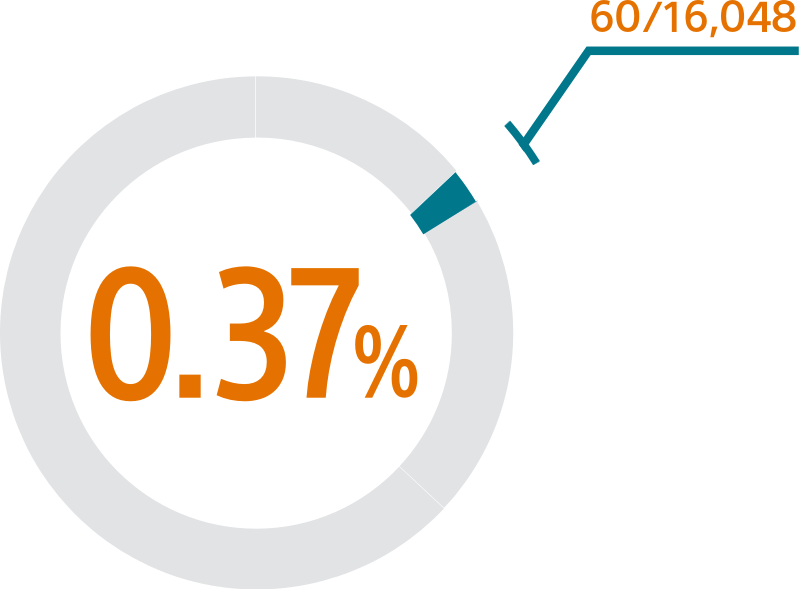

SURPASS demonstrated 0.37% major procedural adverse event rate within 7 days or hospital discharge in 16,048 commercial patients and confirmed the trusted safety profile of WATCHMAN FLX in real-world clinical practice setting.

The SURPASS Data reinforces the excellent safety profile WATCHMAN FLX demonstrated in the PINNACLE FLX Trial, with the largest (n=16,048) real-world WATCHMAN FLX patients studied to date.